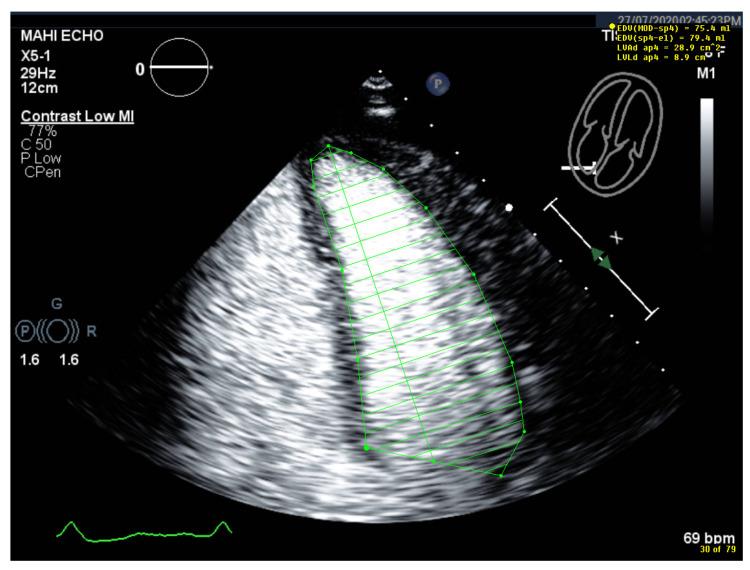

How to Perform Cardiac Contrast-Enhanced Ultrasound (cCEUS): Part I.

Ultrasound enhancing agents (UEAs, formerly called contrast agents) for assessments of the left heart have improved the applicability of echocardiography and the accuracy of echocardiographic measurements. UEAs have been recommended for several diagnostic echocardiographic procedures by national and supernational agencies. The increased use of UEAs during the last years provided more evidence and experience in clinical practice data which is helpful for optimizing the UEA procedures and which will be useful for both newcomers to UEA in echocardiography and sonographers/physicians with experience in echocardiography with UEAs. In two parts, this review focuses on the "how to do" for the approved UEA applications. This is part 1, covering the available UEAs and providing specific guidance on the assessment of global and regional LV function. Part 2 covers the imaging of myocardial disease and masses as well as myocardial perfusion. Recommendations include the application of UEAs in two-dimensional echocardiography as there is limited data on three-dimensional echocardiography. A step-by-step approach is proposed for each of the procedures as well as guidance on how to interpret recordings and how to report them.